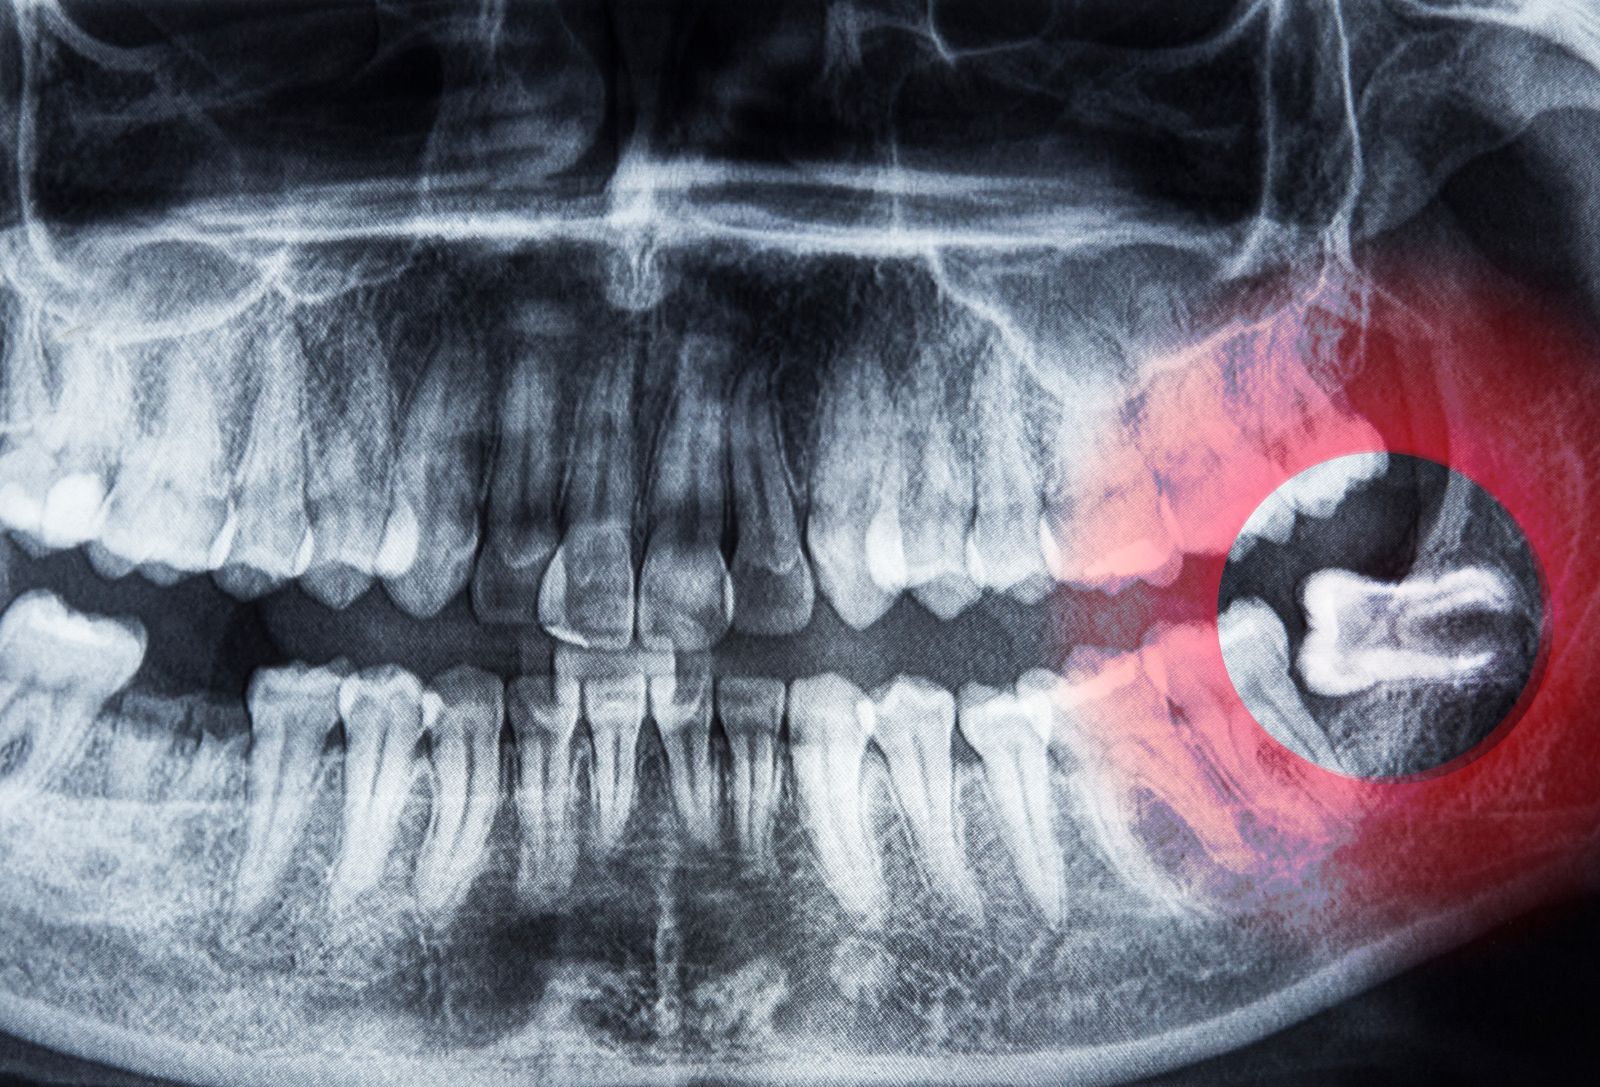

Wisdom teeth are your third molars, located at the back of your mouth. When there isn’t enough space for them to grow properly, they may become impacted, partially erupted, or difficult to clean.

Wisdom molar extraction is recommended when these teeth cause pain, infection, decay, or other oral health issues. The procedure may involve a simple extraction or a surgical removal, depending on the tooth’s position.